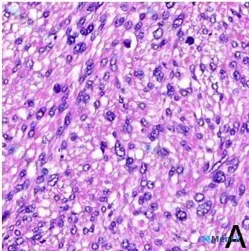

整理到一张病理HE切片的读片资料,先不提供免疫组化和临床背景,看看大家第一眼的思路: > 镜下(HE,×400): > - 肿瘤由梭形细胞构成,核分裂象活跃(16个/10高倍视野) > - 严重弥漫性异型性,核大小不等、形态不规则、深染 > - 胞浆丰富,呈嗜酸性,部分区域可见胞浆空泡化 > - 细...